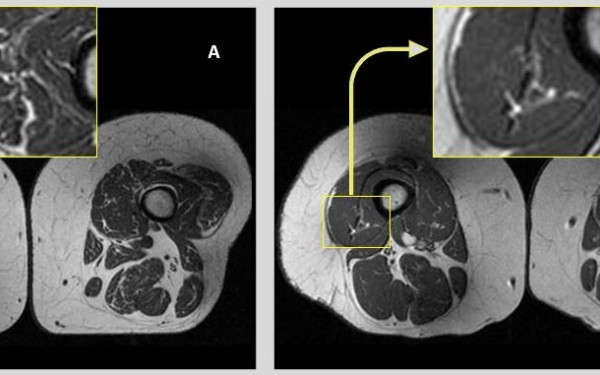

Ερευνητές στη Βόρεια Αμερική έθεσαν ως στόχο να αξιολογήσουν την επίδραση της ποιότητας της διατροφής στο ενδομυικό λίπος

Η έρευνα αποτελεί μέρος μιας ευρύτερης ισπανικής μελέτης που διερευνά την επίδραση της μεσογειακής διατροφής